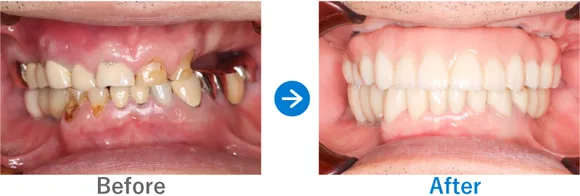

Case4

フルマウスインプラントで、食事も旅行も楽器も楽しめる人生の再スタート!

入れ歯を使用中。重度の歯周病で残っている歯もぐらぐらしている

上顎 オールオン4ダブルザイゴマ、下顎 オールオン4

10,318,000円(上顎6,743,000円、下顎3,750,000円/内訳:上顎オールオン4(ノーベルザイゴマインプラント4本)、下顎オールオン4(ストローマンインプラント4本)、3Dモデルガイド*、仮歯、セデーション、ボツリヌストキシン注射、3D模型、保証10年)

*単体のインプラントのガイドとは異なる、オールオン4専用のガイド

※当時の価格で現在とは異なる場合があります。

来院の背景

入れ歯を作ったものの、重度の歯周病で前歯もぐらぐらしており噛むことが難しく、入れ歯をかけている歯もダメージを受けている状態でした。入れ歯をやめて、友人と気兼ねなく食事をしたり、旅行を楽しんだり、楽器を吹いたりすることをご希望です。

治療結果

ご家族のうち、歯が悪いのは患者さまのみでコンプレックスがあったそうです。今回、思い切って治療を受けてよかった! とおっしゃっていました。30代から糖尿病の治療薬を服用されています。糖尿病は歯周病のリスクが高いので、今後もインプラント周囲炎のリスク管理が重要です。